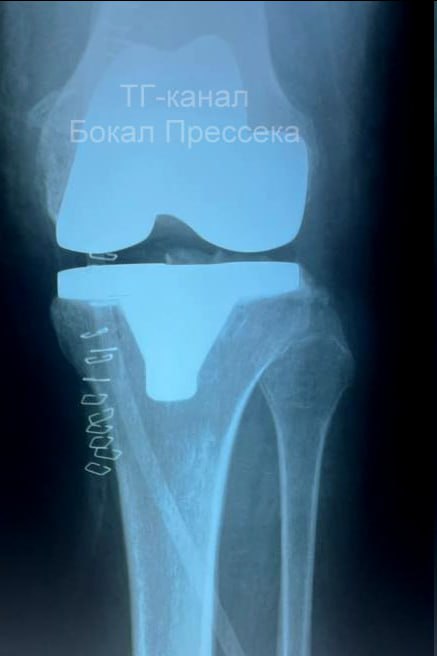

И чудо! Ей установили имплант, всё прошло успешно. Пациентка уже может передвигаться на ходунках, но врачи настоятельно рекомендовали сбросить вес на 10-15 килограммов. Это нужно, чтобы имплант прослужил дольше.